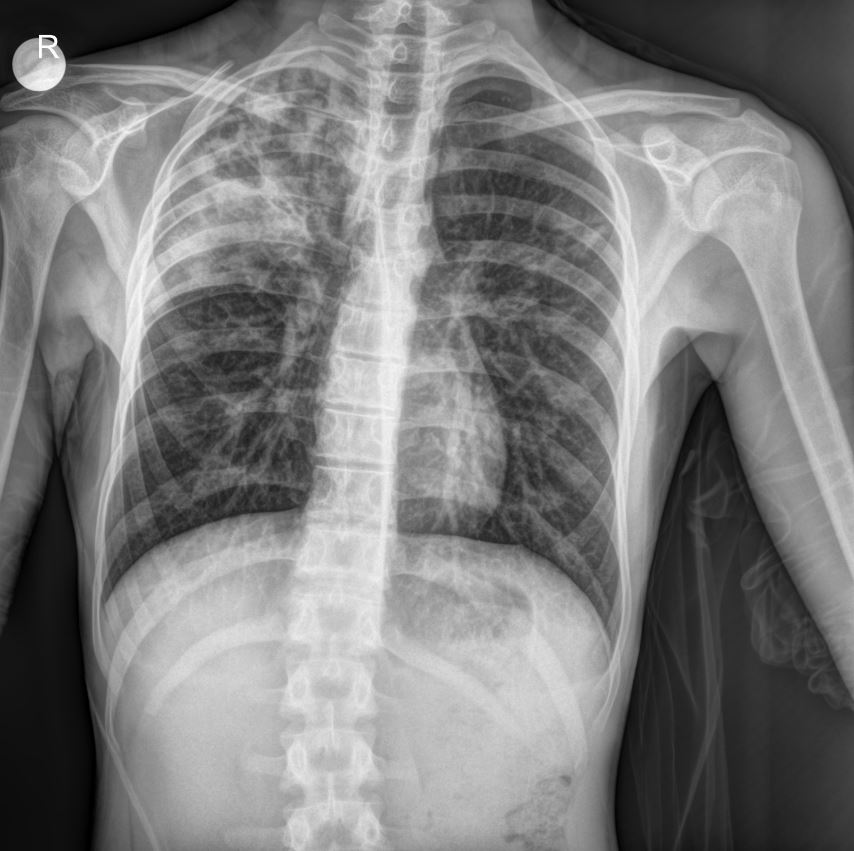

Chest X-ray Findings

The provided chest X-ray image reveals significant findings consistent with bronchopneumonia, particularly in a patient with a history of recurrent respiratory issues.

- Diffuse Parenchymal Infiltrates: The X-ray demonstrates diffuse, patchy infiltrates predominantly in the right lung field, suggesting areas of consolidation and inflammation. These infiltrates are indicative of bronchopneumonia.

- Bronchial Wall Thickening: There appears to be evidence of bronchial wall thickening, which is commonly seen in patients with asthma and chronic respiratory conditions, exacerbated during acute exacerbations or infections like RSV.

- Hyperinflation: While not overtly severe, some degree of lung hyperinflation may be present, which is also a common finding in asthmatic patients.

- Right-sided Predominance: The infiltrates appear more prominent on the right side, aligning with the clinical presentation of respiratory distress.

These radiological findings, coupled with the positive RSV test and clinical symptoms, strongly support the diagnosis of bronchopneumonia in this young patient.

This case highlights the complexities of managing acute respiratory infections like RSV-induced bronchopneumonia in a pediatric patient with a significant history of prematurity, NICU/PICU stays, and pre-existing asthma. The chest X-ray findings visually confirm the presence of parenchymal changes consistent with bronchopneumonia, guiding ongoing management. The multi-faceted approach involving bronchodilators, steroids, antibiotics, and supportive care is crucial in such cases.